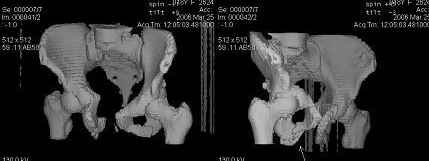

Уважаемые коллеги! Девушка 18л сросшиеся переломы лонных, седалищных костей с обеих сторон, перелом крестца справа,перелом костей голени справа (зио), 3 мес после травмы, АВФ снят с таза. Патологической подвижности нет. Стоит самостоятельно, ходит с костылями, поскольку 3 месяца практически не ходила. Беспокоит выступание лонной кости в области лобка, хотя объективно грубого косметического дефекта нет. На кт разворот лонной кости в сагиттальную плоскость. Вопрос: стоит ли добиватьсяполной репозиции или же достаточно произвести остеотомию верхушки выступающего отломка?

Предварительный диагноз- посттравматическая вертикальная нестабильная деформация таза II степени, неправильно срастающийся перелом боковой

массы крестца справа, правой лонной и седалищной костей, застарелый разрыв лонного сочленения.

Для уточнения диагноза ниеобходимы обзорные рентгенограммы таза (прямая и inlet), Кт срезы на уровне переломов для определения степени сращения и решения вопроса о методе оперативного восстановления анатомии (делать ли остеотомию, низводить ли задние отделы), ни о какой "остеотомии выступающих отломков" тем более у девочки 18 лет речи быть не может.

При более детальном распросе, наверное, удастся обнаружить и другие жалобы, либо они появятся при увеличении нагрузок. Как представляется, задачей лечения будет являться восстановление целостности и стабильности тазового кольца. Оптимальным вариантом может быть низведение левой половины таза, затем реконструкция передних отделов. Варианты выполнения репозиции и фиксации - тема отдельного разговора.